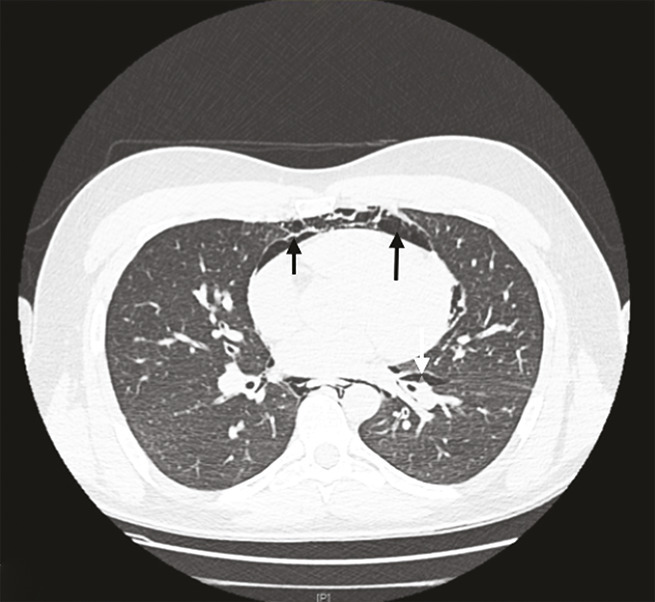

Un homme de 25 ans, sans autre antécédent qu’un tabagisme actif, a ressenti, au décours d’un repas, une douleur cervicale accentuée par la déglutition et une sensation de gêne respiratoire. Il décrivait une atteinte rhinopharyngée peu intense avec une toux grasse depuis 48 heures. Aux urgences, son état hémodynamique n’inspirait pas d’inquiétude, avec une pression artérielle à 151/85 mmHg, une fréquence cardiaque à 90 batt/min, une saturation en oxygène en air ambiant à 95 % et une fréquence respiratoire à 20 cycles/min. Il n’existait pas de notion d’effort à glotte fermée, ni de prise de toxique. L’examen clinique a révélé une rhinopharyngite banale mais surtout un emphysème sous-cutané sus-claviculaire droit (signe de Minnigerode : présence d’air dans la région para-œsophagienne du cou). La radiographie thoracique a mis en évidence un emphysème sous-cutané ainsi qu’un pneumomédiastin (fig. 1 et 2 ). Le patient a été hospitalisé 24 heures dans un service de post-urgence pour surveillance et prise en charge de la douleur. Le scanner thoracique, réalisé le lendemain, a confirmé un pneumo-médiastin de faible abondance ainsi qu’un minime pneumothorax scissural gauche (fig. 3 ). L’état de santé du patient a été réévalué en consultation de pneumologie quatre jours plus tard. L’évolution a été favorable.

Le pneumomédiastin est rare (incidence : 4/100 000) et plus encore s’il est associé à un pneumothorax (1,5 % des pneumomédiastins),1, 2 comme dans le cas de ce patient. L’augmentation de la pression dans les voies respiratoires peut être responsable de pneumomédiastin.3 L’imagerie confirme le diagnostic, notamment la radiographie thoracique. Cette pathologie, très souvent bénigne, nécessite un traitement antalgique et une surveillance simple.